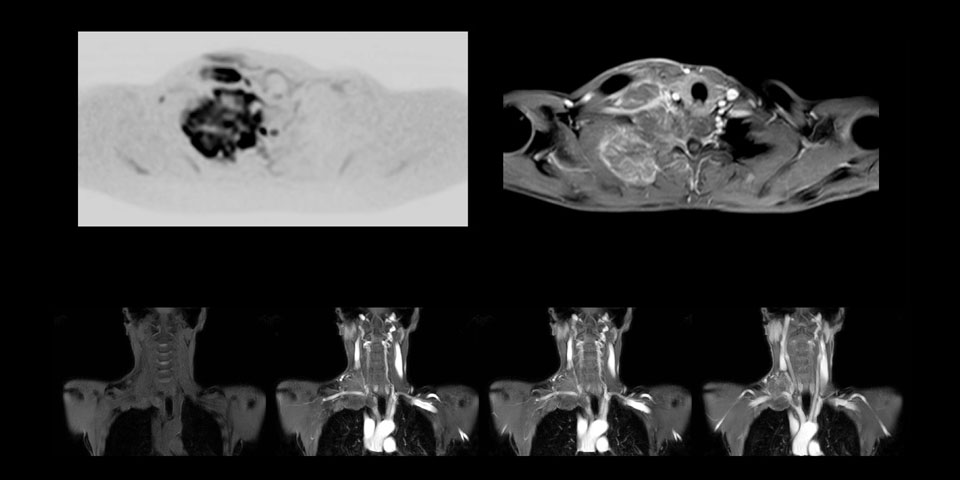

Although the area between the neck and the top of the lung is one of the most difficult areas for MRI, Prodiva 1.5T images show good quality in this 56-year-old male with Pancoast tumor on the right. mDIXON TFE images shows excellent fat suppression in the neck area and the DWI shows almost no distortion.

A 61-year-old female with a malignant lymphoma underwent an MRI exam with whole body diffusion weighted imaging (DWIBS) as well as PET. On the images shown, the resolution of DWIBS is better than PET, which allows visualization of the small pelvic lesions and almost no distortion is seen in the neck area.